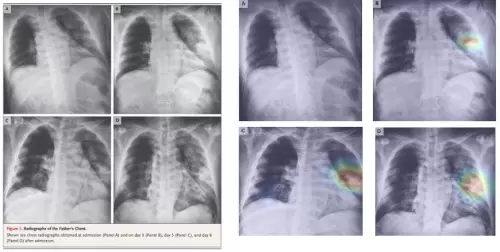

今年3月,致力于影像学深度学习研发的点内科技,为了满足国际医疗需求,在持续追踪和研究新冠肺炎病例后,在对既有的近 40 万例多中心、多病种X-Ray 影像辅助筛查算法技术的基础上,利用迁移学习技术和新冠肺炎数据开发了“点内AI 新冠肺炎X-ray分析平台”。该平台的AI算法模型已经通过顶级期刊 Nature、柳叶刀、新英格兰医学等杂志论文中公开的新冠确诊病例 X 光胸片数据进行验证,敏感度大于 95%,且病程发展和病灶位置与实例吻合。

(上图:在顶级期刊 Nature 上发表的 X 光胸片案例与点内科技“点内AI 新冠肺炎X-ray分析平台”分析结果比较)

(上图:顶级期刊《柳叶刀》上的阳性案例与点内科技“点内AI 新冠肺炎X-ray分析平台”分析结果比较)

(上图:顶级期刊《新英格兰杂志》上的新冠阳性案例与点内科技“点内AI 新冠肺炎X-ray分析平台”分析结果比较)